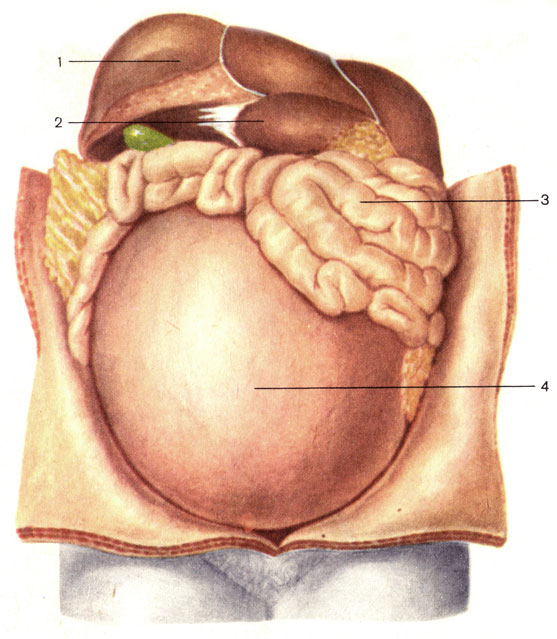

Физиология беременности: строение органов

Раздел: Моменты озарения